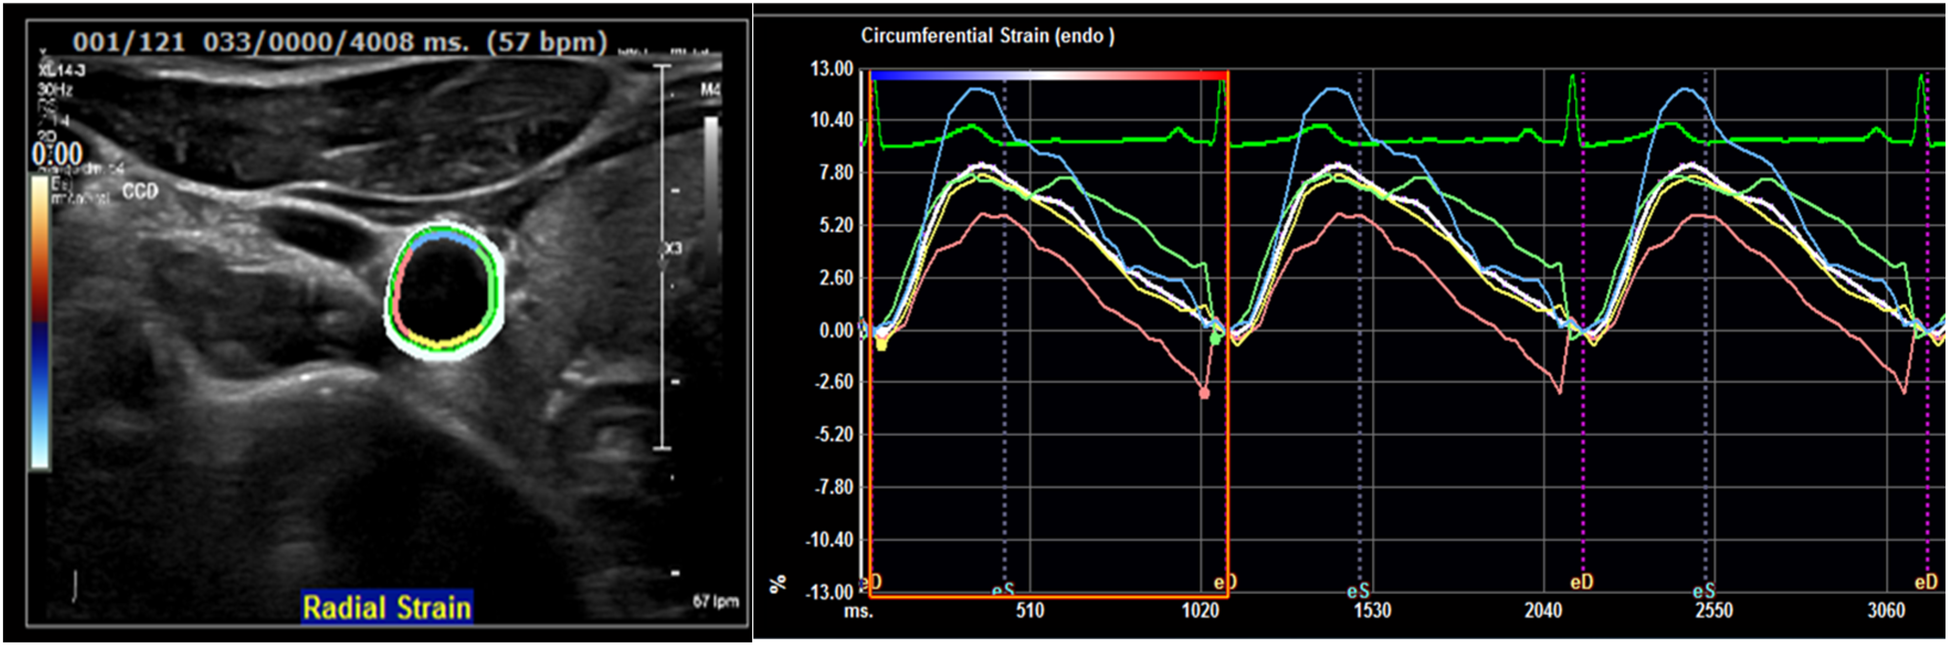

Vascular ultrasound imaging will be carried out using Philips EPIQ Elite 7.0.5 and the protocol includes 2D VUS of the carotid, aorto-iliac and femoral territories (cross-sectional and longitudinal images) and 3D VUS of any plaque (volume set) with an approximate examination time of 40 min (Figure 2). Imaging analysis will include plaque presence, thickness, volume and degree of stenosis (5). Strain-rate measurements of the carotid cross-sectional image will also be assessed to increase our understanding of the elastic properties and function of the arterial walls providing potential information on arterial health status by analyzing distensibility/compliance coefficients, b-stiffness index, circumferential strain/strain rate, peak radial velocity (Figure 3) (32).

Figure 3

Carotid arterial strain curves with different colors representing the four arterial segments included in strain analysis the white line represents average radial strain.